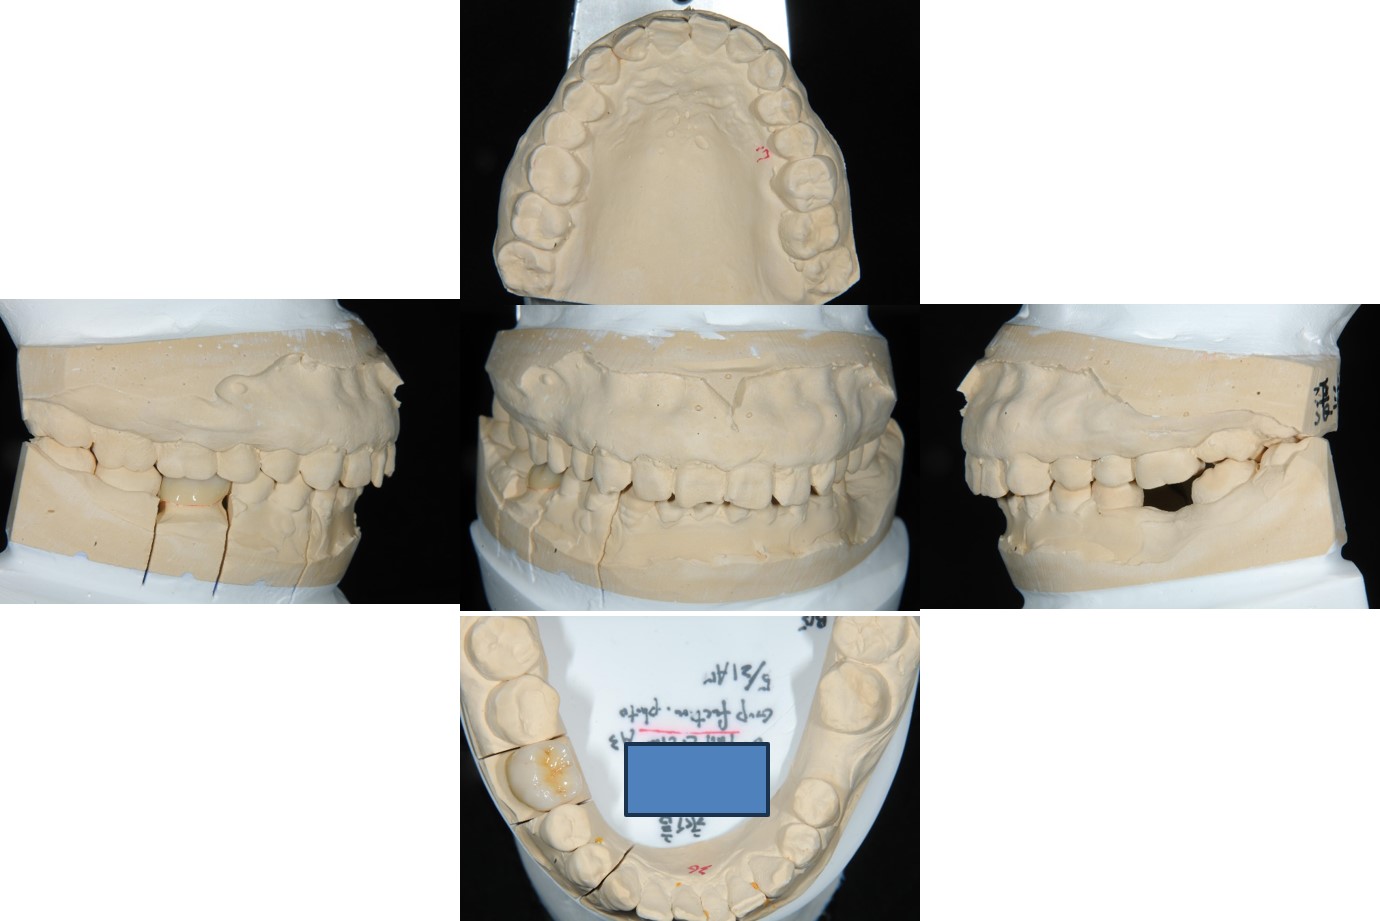

上面弓、上咬合器

技師於咬合器製作全瓷冠